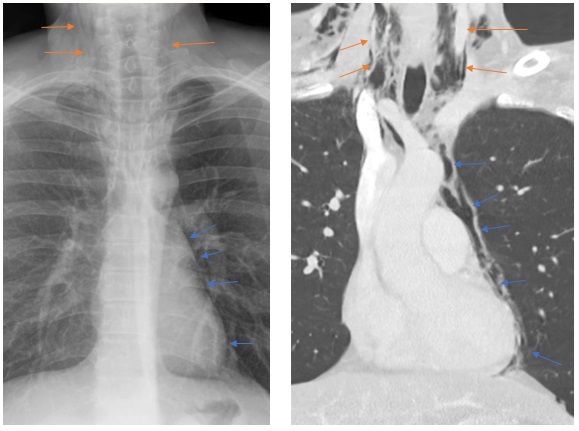

Dentro de los métodos diagnósticos, el neumomediastino se puede diagnosticar mediante radiografías o tomografía computada, donde se va a visualizar la presencia de aire (radiolucidez o hipodensidad lineales) rodeando las estructuras mediastinales. Un signo de muy alta especificidad es el llamado “signo del anillo alrededor de la arteria”, donde se visualiza una imagen radiolúcida o hipodensa en forma de anillo rodeando la arteria pulmonar, principalmente del lado derecho. Este signo ayuda a diferenciar esta entidad del neumopericardio, que puede verse similar en imágenes.

Among the diagnostic methods, pneumomediastinum can be diagnosed using X-rays or computed tomography scans, where the presence of air (linear radiolucency or hypodensity) surrounding the mediastinal structures will be visualized. A highly specific sign is the so-called “ring sign around the artery”, where a radiolucent or hypodense ring-shaped image is visualized surrounding the pulmonary artery, primarily on the right side. This sign helps differentiate this condition from pneumopericardium, which can appear similar on imaging.